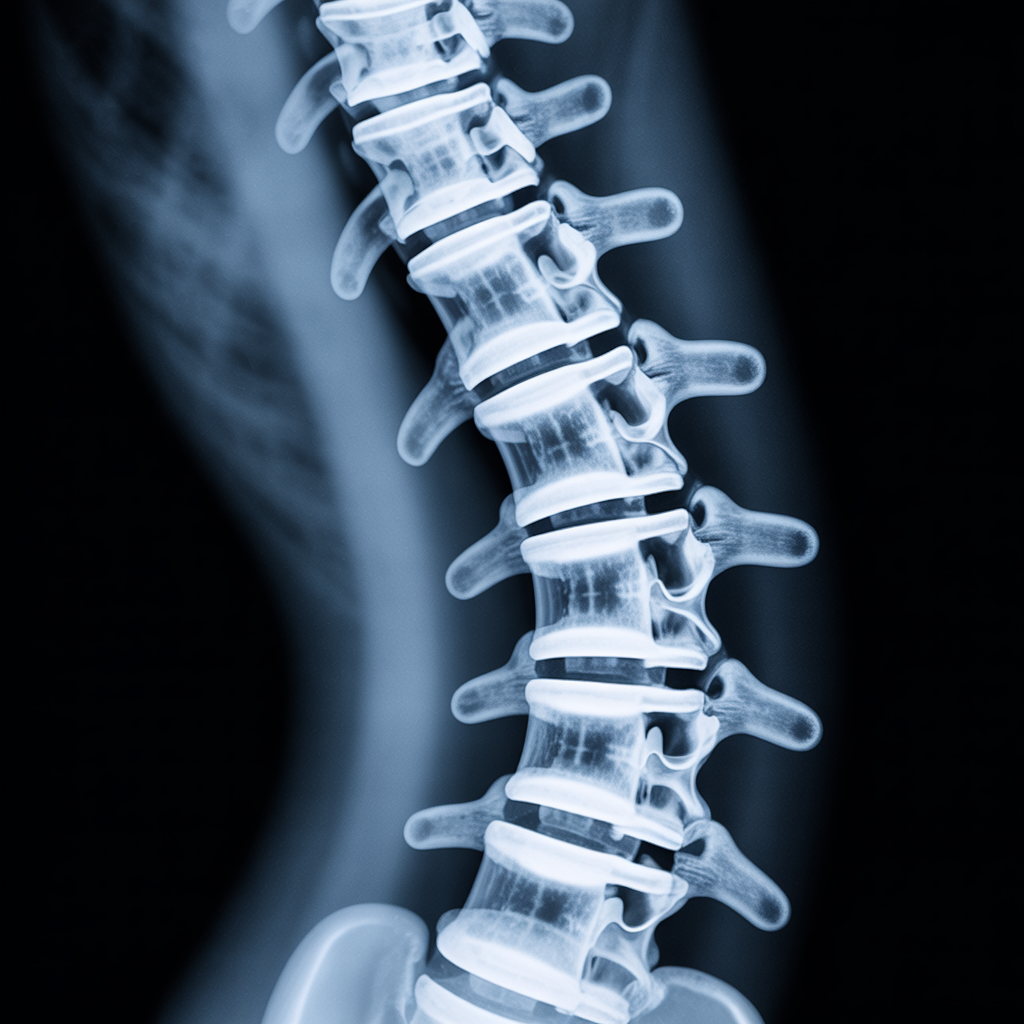

Die Knochenmineraldichte (Bone Mineral Density, BMD) gibt an, wie „fest“ die Knochensubstanz ist und spielt eine entscheidende Rolle für die Stabilität des Skeletts. Insbesondere für SportlerInnen ist eine ausreichende BMD wichtig, da intensive Belastungen, Sprünge und hohe Trainingsumfänge die Knochen beanspruchen und ein Mangel zu Brüchen oder Stressfrakturen führen kann.

- Knochendichtemessungen (DXA-Scan, Z-Score).